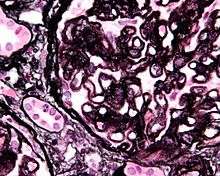

-

Renal corpuscle. GBM is #1.